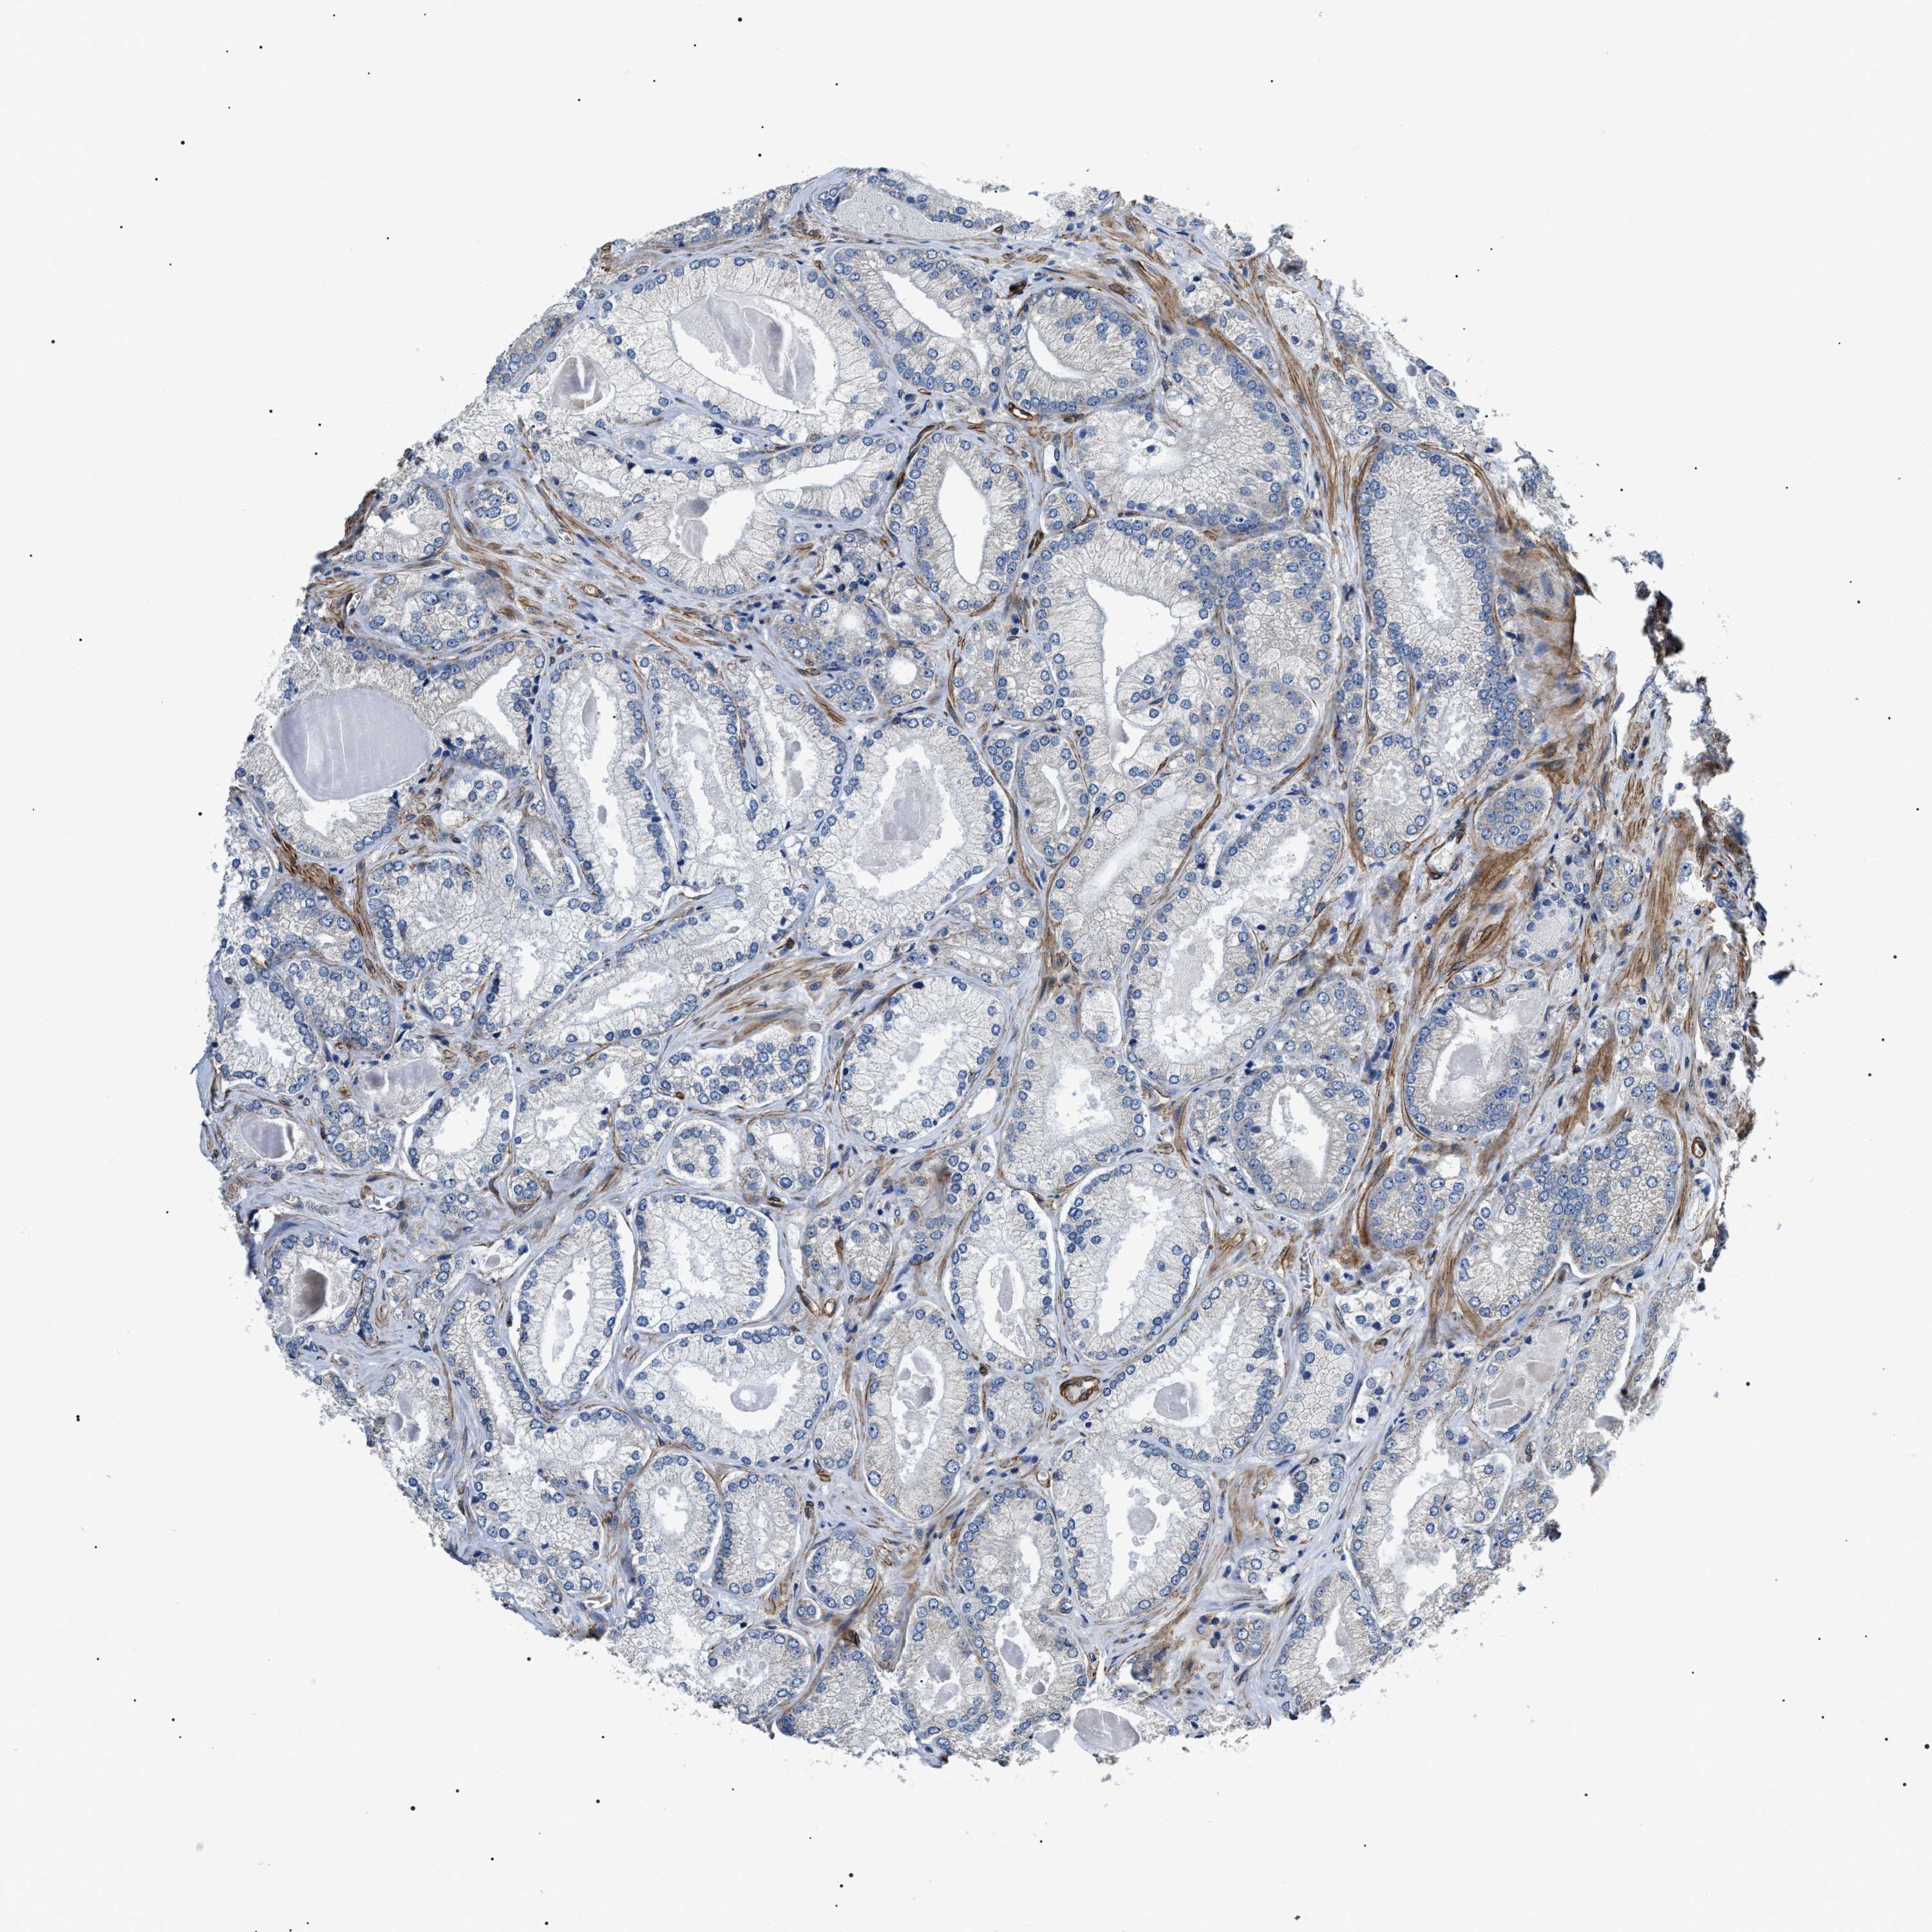

PROSTATE CANCER - Protein expressioni

A mouse-over function shows sample information and annotation data. Click on an image to view it in a full screen mode. Samples can be filtered based on level of antibody staining by selecting one or several of the following categories: high, medium, low and not detected. The assay and annotation is described here.

Note that samples used for immunohistochemistry by the Human Protein Atlas do not correspond to samples in the TCGA dataset.

Antibody stainingi

Antibody staining in the annotated cell types in the current human tissue is reported as not detected, low, medium, or high, based on conventional immunohistochemistry profiling in selected tissues. This score is based on the combination of the staining intensity and fraction of stained cells.

Each image is clickable and will lead to virtual microscopy that enables deeper exploration of all samples and also displays staining intensity scores, fraction scores and subcellular localization as well as patient and tissue information for each sample.

Antibody HPA020386

Staining

High

Medium

Low

Not detected

Intensity

Strong

Moderate

Weak

Negative

Quantity

>75%

75%-25%

<25%

None

Location

Nuclear

Cytoplasmic/membranous

Cytoplasmic/membranous,nuclear

Adenocarcinoma, High grade

Adenocarcinoma, Low grade